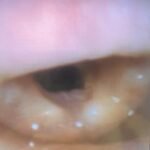

This is a case report of a 55-year-old woman with a past medical history of hypertension who presented to the emergency department with upper lip and cheek swelling isolated to the right side of her face. She was on lisinopril for several years and had never had an episode of swelling in the past. Her vital signs were stable. However, on reassessment, the patient’s right sided swelling progressed to the entire upper lip and she complained of swelling in her submandibular space. Although no swelling was appreciated to the submandibular space on physical exam, and the patient still did not have any signs or symptoms of respiratory distress, the decision was made to use a fiberoptic laryngoscope to evaluate her airway. Fiberoptic laryngoscope showed noticeable laryngeal edema which did not improve after treatment, and the patient was admitted to the medical intensive care unit for close airway observation. This case highlights the use of fiberoptic laryngoscope by emergency physicians in the evaluation of patients with relatively benign appearing angioedema.